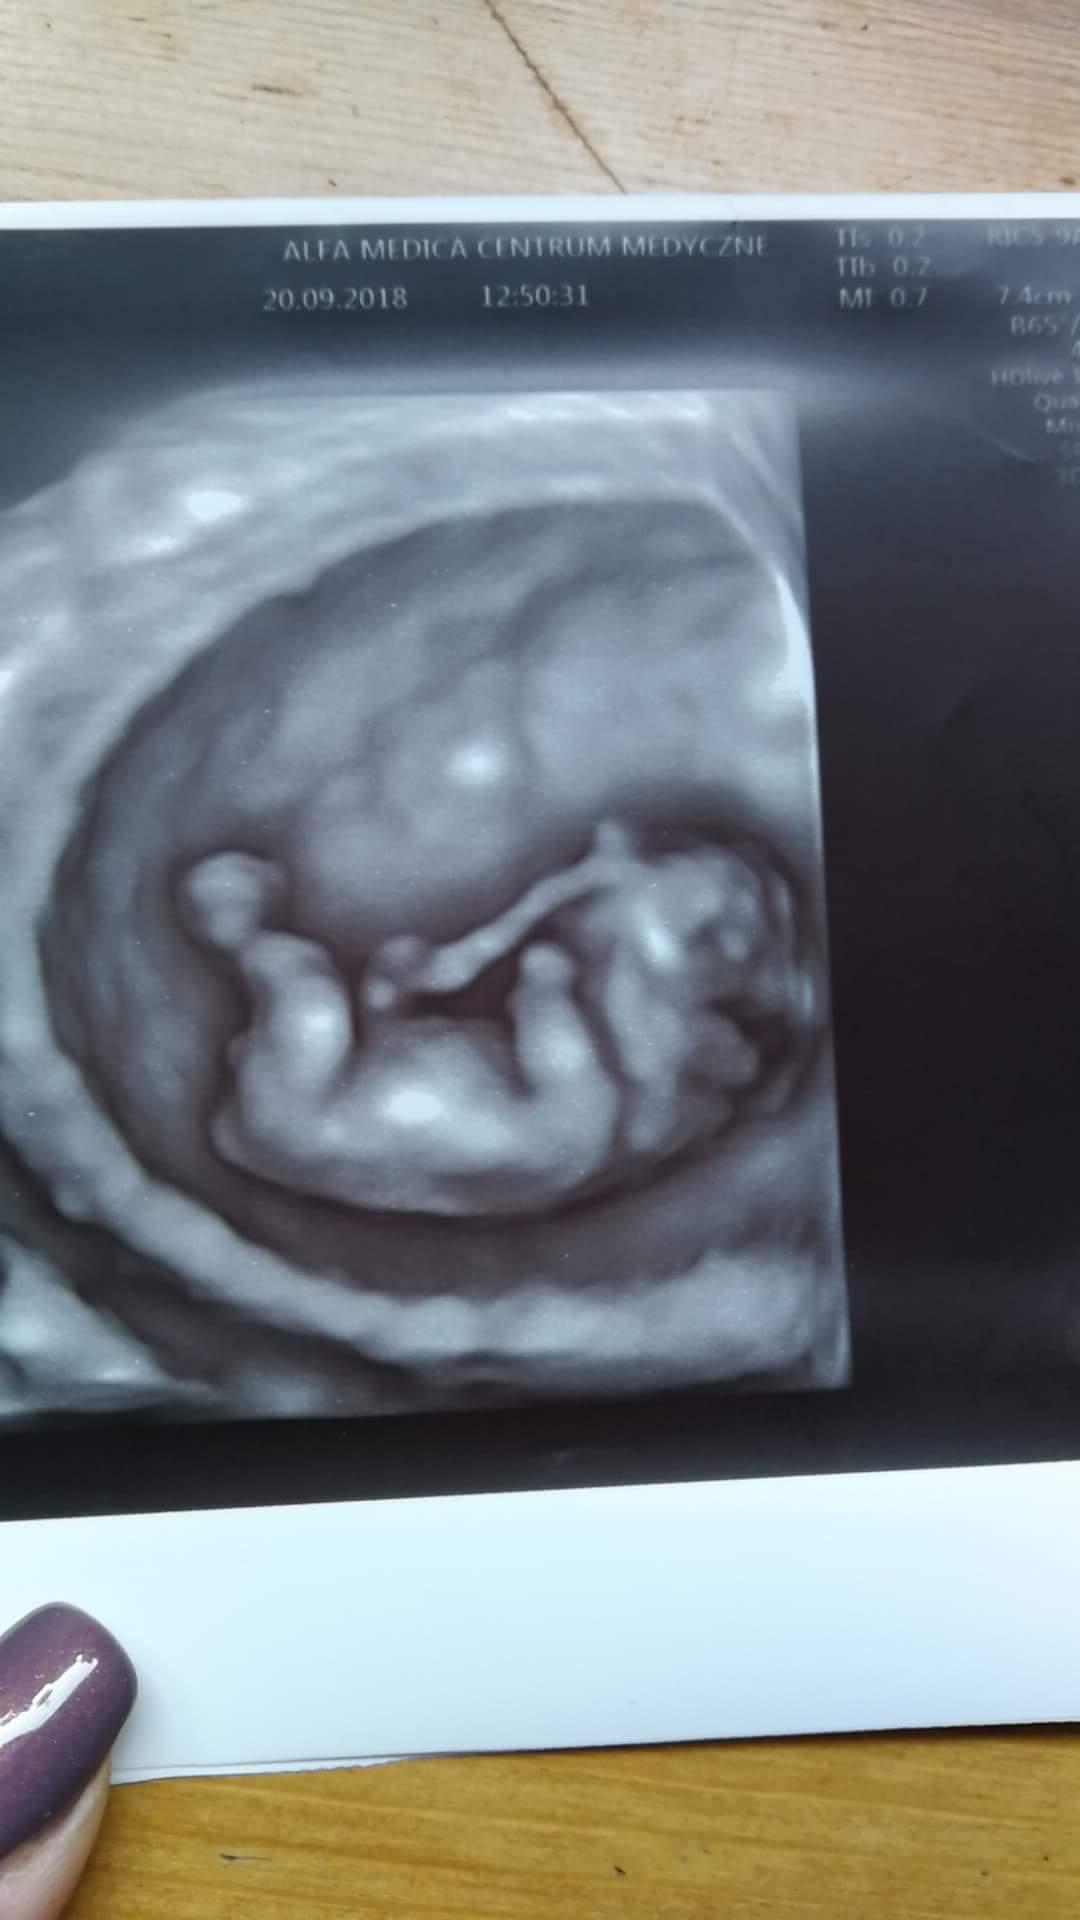

No więc wreszcie w miarę sie uspokoiłam i na spokojnie mogę opisać moją wczorajszą wizytę. Przyjeła nas bardzo miła specjalistka od usg, przy okazji posprawdzala jajniki, łożysko, pepowine, macice itd. Ostatnim razem w bristolu Pani sprawdziala tylko dzidziusia, usg trwalo moze 2 minutki. Tym razem wszystko bylo wyswietlane na duzym ekranie zawieszonym pod sufitem. Wtedy pokazała nam naszego malutkiego człowieczka, całe 2,81 cm :) Nie spodziewaliśmy się i nagle maluszek zaczal podkakiwac, ruszać rączkami i nóżkami, było to tak wzruszajace ze nie ma jak tego opisać, łzy lały sie litrami. Na koniec dostalismy cudowny filmik z całym usg i naszym fikołkiem ;) Data porodu przesunieta z 19 na 20 kwietnia. Myślę że teraz jestem juz gotowa przedstawic Wam moje malenstwo.

20180920_161355.jpg